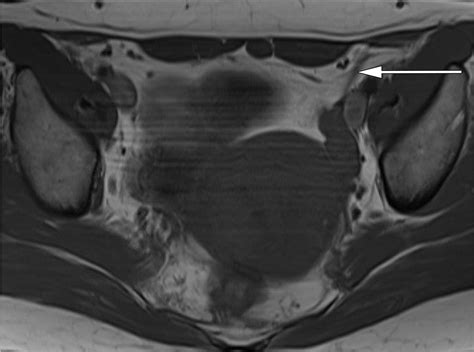

Magnetic Resonance Imaging (MRI)

MRI is a powerful imaging technique that uses magnetic fields and radio waves to create detailed images of internal structures. It provides excellent soft tissue contrast and can be used to visualize the Ovary Suspensory Ligament and surrounding tissues. MRI is particularly useful for detecting tumors or other abnormalities within the ligament.

Imaging studies, such as ultrasound, MRI, or CT scans, can help visualize the Ovary Suspensory Ligament and assess its involvement in various conditions. For example, imaging can detect abnormalities in the ligament, such as inflammation, tumors, or vascular anomalies.